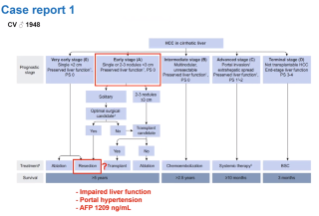

How SIRT can fill the gaps? Can SIRT lead to curative treatment in HCC?

Oct 07, 2020

External Link( 23.0 MB )

Dr Droz Dit Busset discussed the place of SIRT in the current HCC treatment algorithm and whether it can lead to cure.